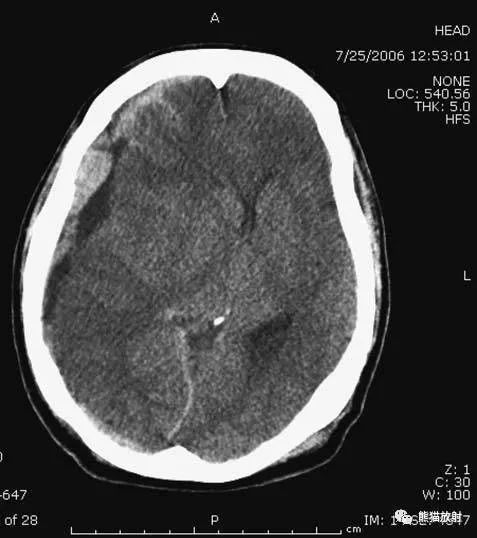

A:陈旧性脑梗死,右枕叶体积缩小;

B:左枕叶急性脑梗死,灰白质分界模糊,脑沟消失;

另一患者:

C、D:亚急性期脑梗死,低密度,无明显占位效应。

▲左侧大脑中动脉供血区脑梗死(亚急性期):

低密度,轻度水肿。

缺血性脑卒中发作2-4天时,占位效应最明显。